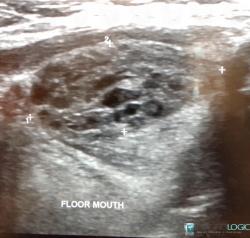

18 yr old for USG neck- Altered thyroid funtion See more

Lingual thyroid( ectopic thyroid) with secondary colloid goiter changes See more